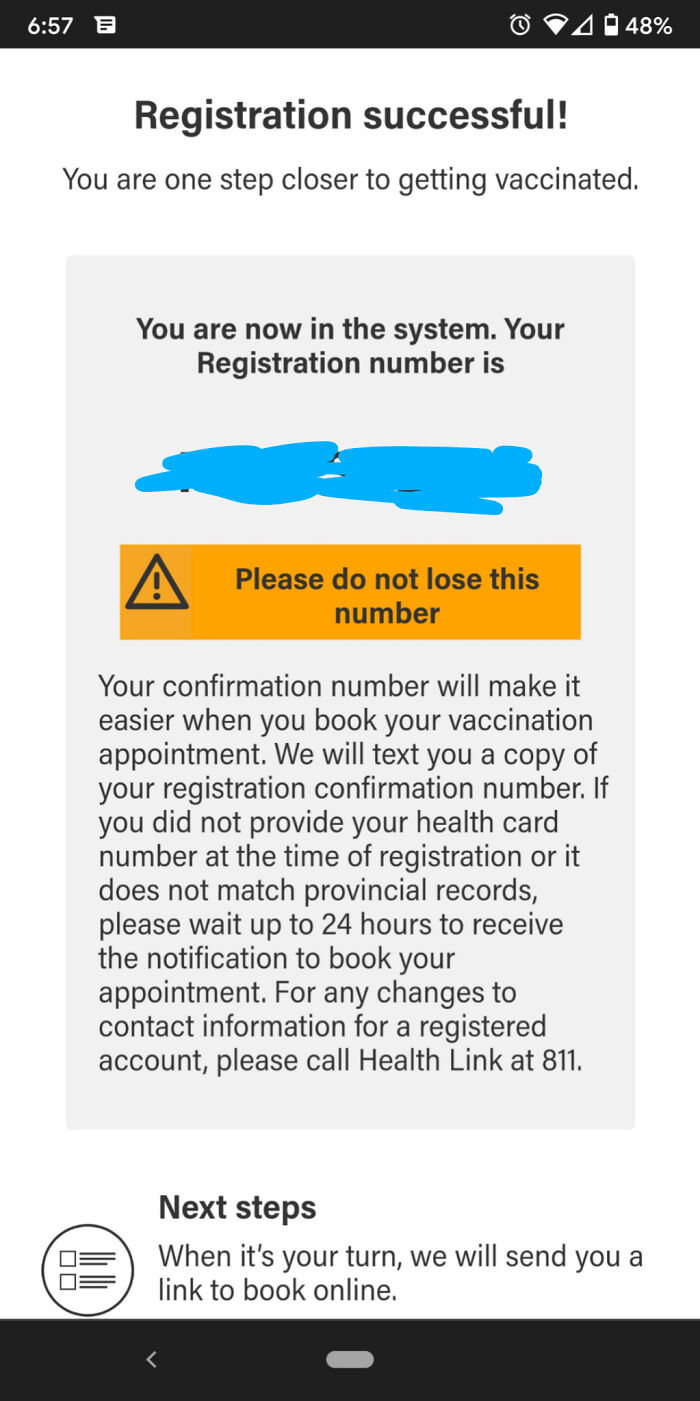

Got My Third Covid Shot Yesterday